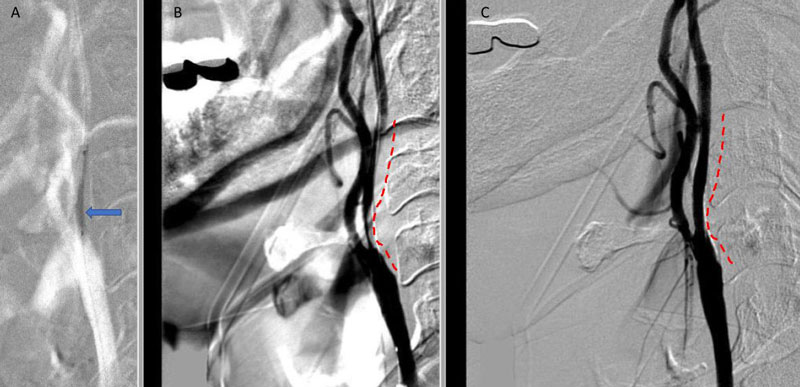

An MRI confirmed diffusion and FLAIR positive ischemic strokes within the deep periventricular white matter compatible with a “watershed” distribution of injury (Figure 3).

Figure 3. A) MRI Diffusion and B) FLAIR sequence confirm ischemic damage in the right periventricular deep white matter “Watershed” territories.